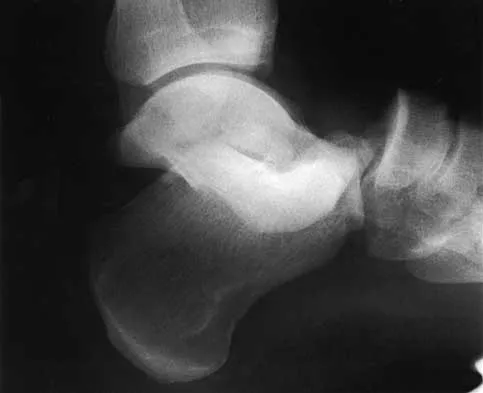

A 42-year-old woman sustained a closed, displaced talar neck fracture in a motor vehicle accident. Which of the following is an avoidable complication of surgical treatment?

Explanation

Malunion of the talus is a devastating complication that leads to malpositioning of the foot and subsequent arthrosis of the subtalar joint complex. This is considered an avoidable complication in that accurate surgical reduction will minimize its development. Posttraumatic arthritis of the subtalar joint, osteonecrosis of the talus, posttraumatic arthritis of the ankle joint, and complex regional pain syndrome all may develop as a result of the initial traumatic event and may not be avoidable despite anatomic reduction. Rockwood and Green's Fractures in Adults, ed 5. Philadelphia, PA, Lippincott, Williams and Wilkins, 2001, pp 2091-2132.

- Daniels TR, Smith JW, Ross TI: Varus malalignment of the talar neck: Its affects on the position of the foot and on subtalar motion. J Bone Joint Surg Am 1996;78:1559-1567.